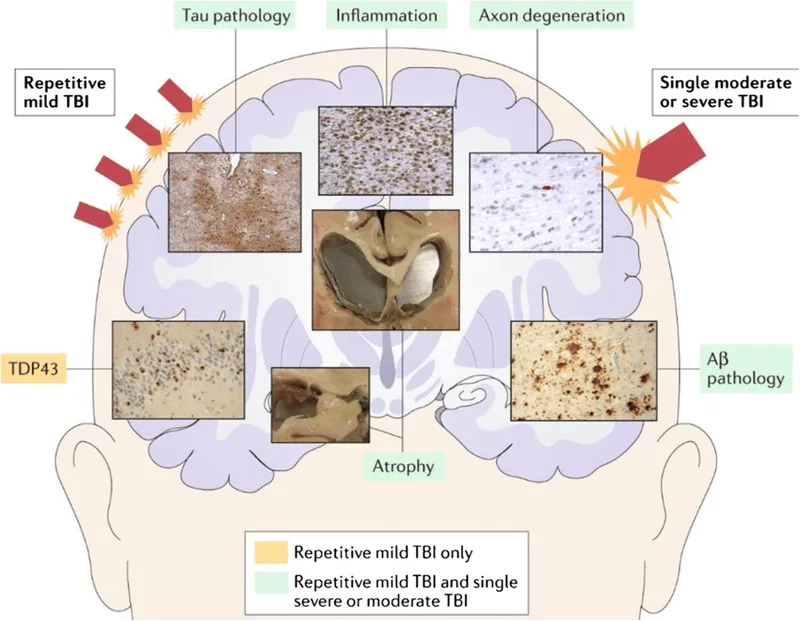

- The primary answer to what causes CTE is repetitive head trauma, including both concussive and sub-concussive impacts, sustained over many years of exposure.

- The accumulation of an abnormal protein called tau forms clumps that slowly spread throughout the brain, killing brain cells and leading to progressive decline.

Visualizing concepts related to CTE